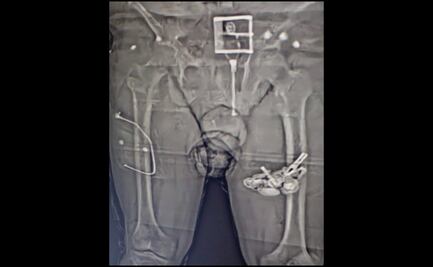

Las imágenes captadas por una cámara denominada “Bodyscan” detectaron que una persona llevaba entre su ropa interior diversos paquetes